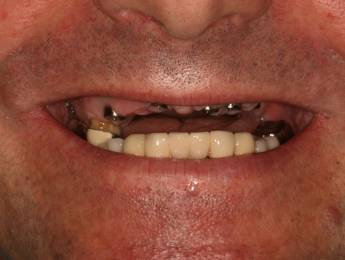

Implantátumok előtte-utána

Fogászati implantátumok előtte-utána

Implantátum beültetés előtt és után

A FOGBEÜLTETÉS MENETE

Az eljárás megkezdése előtt a páciens helyi érzéstelenítést kap, amely garantálja, hogy a kezelés teljesen fájdalommentes lesz. A sebész fölnyitja az ínyt, behelyezi az implantátum csavarjait, és összevarrja a területet. Időre van szükség, hogy ezek a csavarok jól beágyazódjanak, emiatt néhány hónapot várni kell, mielőtt fel lehet helyezni a koronát. Hogy elkerüljük a fog nélkül maradást, a páciens erre az időre egy ideiglenes protézist kap, így enni és mosolyogni is tud.

Amennyiben az íny megfelelően begyógyult, lenyomatot veszünk és elkészítjük a hidat, vagy koronát. Ez kerül a kezelés végén az implantátumra, ez lesz a végleges fogsor.